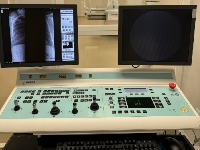

Мобильный рентгенаппарат + оцифровщик. Получение рентгеновского изображения на экране ноутбука. Вариант за 1,4 миллиона рублей под ключ.

Мобильный рентгенаппарат с печатью рентгенограмм на рентгеновской пленке. Цена 700000 рублей.

Радиационно-гигиенические паспорта и отчеты №1-ДОЗ №3-ДОЗ для предприятий из Москвы и регионов РФ - оформление документов. Как правильно оформить отчеты №1-ДОЗ №3-ДОЗ за 2024 год

Получение санитарно-эпидемиологическое заключение на осуществление деятельности в области работы (ИИИ).